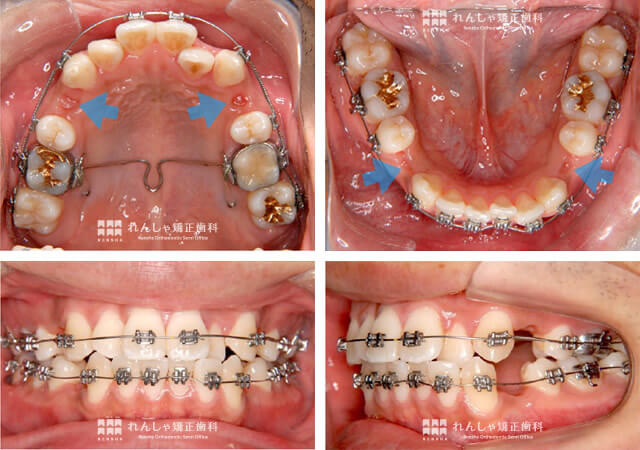

歯のがたつきが改善したので今後は上下前歯を後方へ牽引する

以下の症例写真のように、S.Tさんのがたつきの改善は進んでいます。今後は、残ったスペースを利用して上下前歯を後方へ牽引していく治療を行います。

治療途中では上下前歯の真ん中がずれてしまうこともありますが、最終調整では極力合わせるようにします。